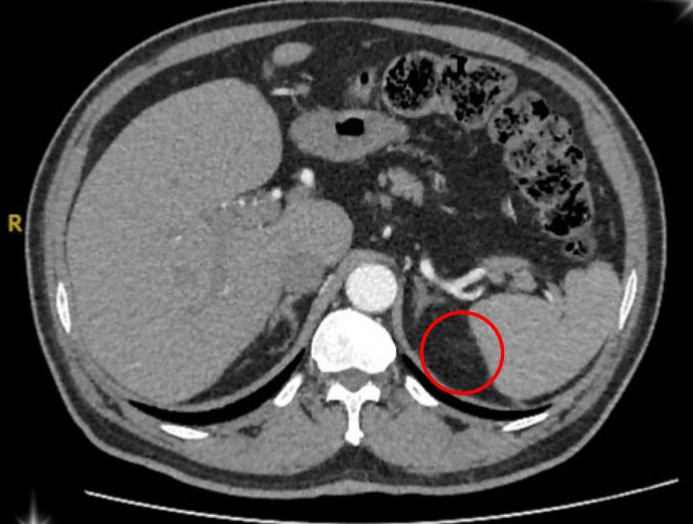

Hình ảnh vùng ổ bụng của bệnh nhân u tuyến thượng thận. Ảnh: BVCC

Sau quá trình kiểm tra kỹ lưỡng, ông T. được xác định mắc phải hội chứng Conn (hay còn gọi là cường Aldosterone tiên phát) – một bệnh lý hiếm gặp do khối u nhỏ ở vỏ tuyến thượng thận gây ra.

Theo BS. Đinh Công Thịnh – Bác sĩ Khoa Ngoại Tiết Niệu, tuyến thượng thận là cơ quan nội tiết nhỏ nằm phía trên thận, đóng vai trò quan trọng trong việc sản xuất hormone giúp điều hòa huyết áp, cân bằng nước, điện giải và kiểm soát quá trình chuyển hóa của cơ thể.

Khi xuất hiện khối u, tuyến này tăng cường tiết ra aldosteron (là hormone giúp điều hòa natri và kali trong máu). Khi lượng hormone này tăng quá mức, người bệnh sẽ rơi vào tình trạng tăng huyết áp kéo dài, hạ kali máu, mệt mỏi, đau đầu, chuột rút, thậm chí rối loạn nhịp tim.